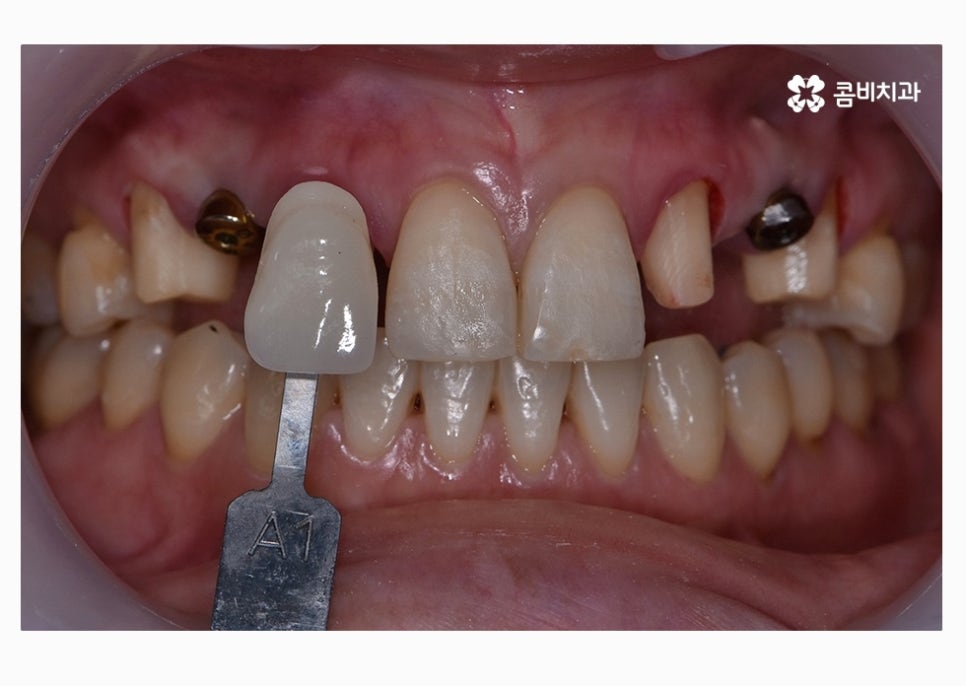

오늘 보실 30대임플란트 환자분의 사례는

윗니 2개를 충치로 인해 잃게 되어 임플란트를 하게 되었으며

아랫니가 벌어져 있고 치열이 고르지 못해서

치아 관리에 어려움을 느꼈기 때문에 치아 건강과

심미적인 치열을 위해서 치아교정도 함께 진행된 사례라고 할 수 있어요.

위에 표시된 치아는 이미 발치가 된 상태에서 임시치아를

부착하고 생활을 하셨던 환자이며 고르지 못한 치열을

개선하고 임시치아를 부착한 치아에 임플란트를 식립한 사례라고 할 수 있어요.

자세히 보시면 임시치아라는 것을 알 수 있고 엑스레이

사진을 보면 더 자세히 알 수 있습니다.